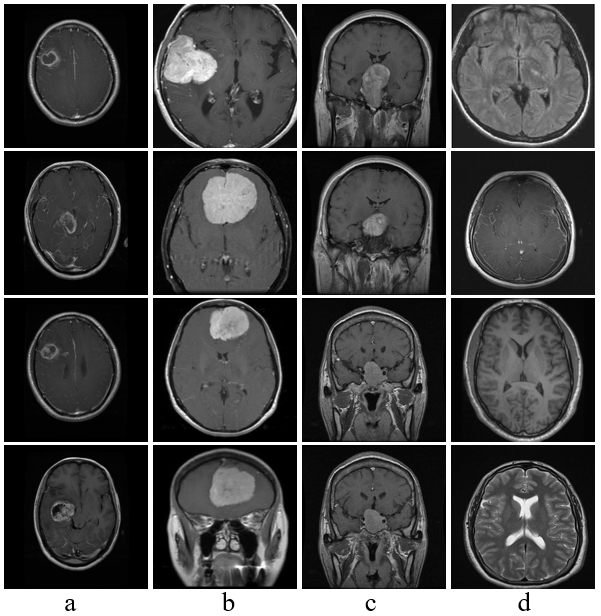

| 图6 从Dataset-1和Dataset-2数据集中抽取的正常与肿瘤脑部影像的样本. a: 胶质瘤; b: 脑膜瘤; c: 垂体瘤; d: 无肿瘤 |

| Fig. 6 Samples of normal and tumor brain images extracted from Dataset-1 and Dataset-2. a: Glioma, b: Meningioma, c: Pituitary, d: No tumor |